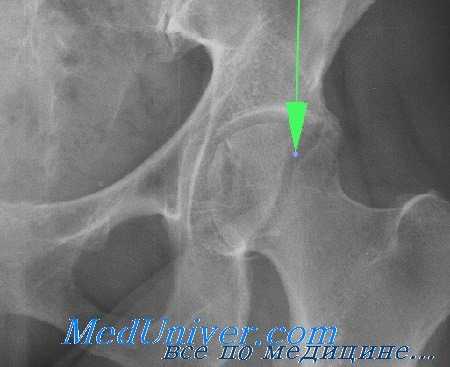

Для выявления переломов этого типа достаточно, как правило, обычных рентгенограмм в прямой проекции и в проекции с наружной и внутренней ротацией бедра. Диагностике скрытых переломов часто помогают рентгенограммы в сравнительных проекциях. У всех больных с подозрением на перелом бедра должна быть тщательно изучена линия Шентона. Кроме того, при подозрении на перелом необходима оценка шеечно-диафизарного угла, который в норме составляет 120—130°. Его измеряют от точки линий пересечения, проведенных по осям диафиза и шейки бедренной кости.

Класс А: перелом головки бедренной кости

Перелом головки бедренной кости встречается редко и может проявиться в сочетании с вывихом или без какой-либо значительной деформации. Его классифицируют по двум типам на основании размера и количества фрагментов. При переломах I типа имеется один фрагмент, в то время как переломы II типа являются оскольчатыми.